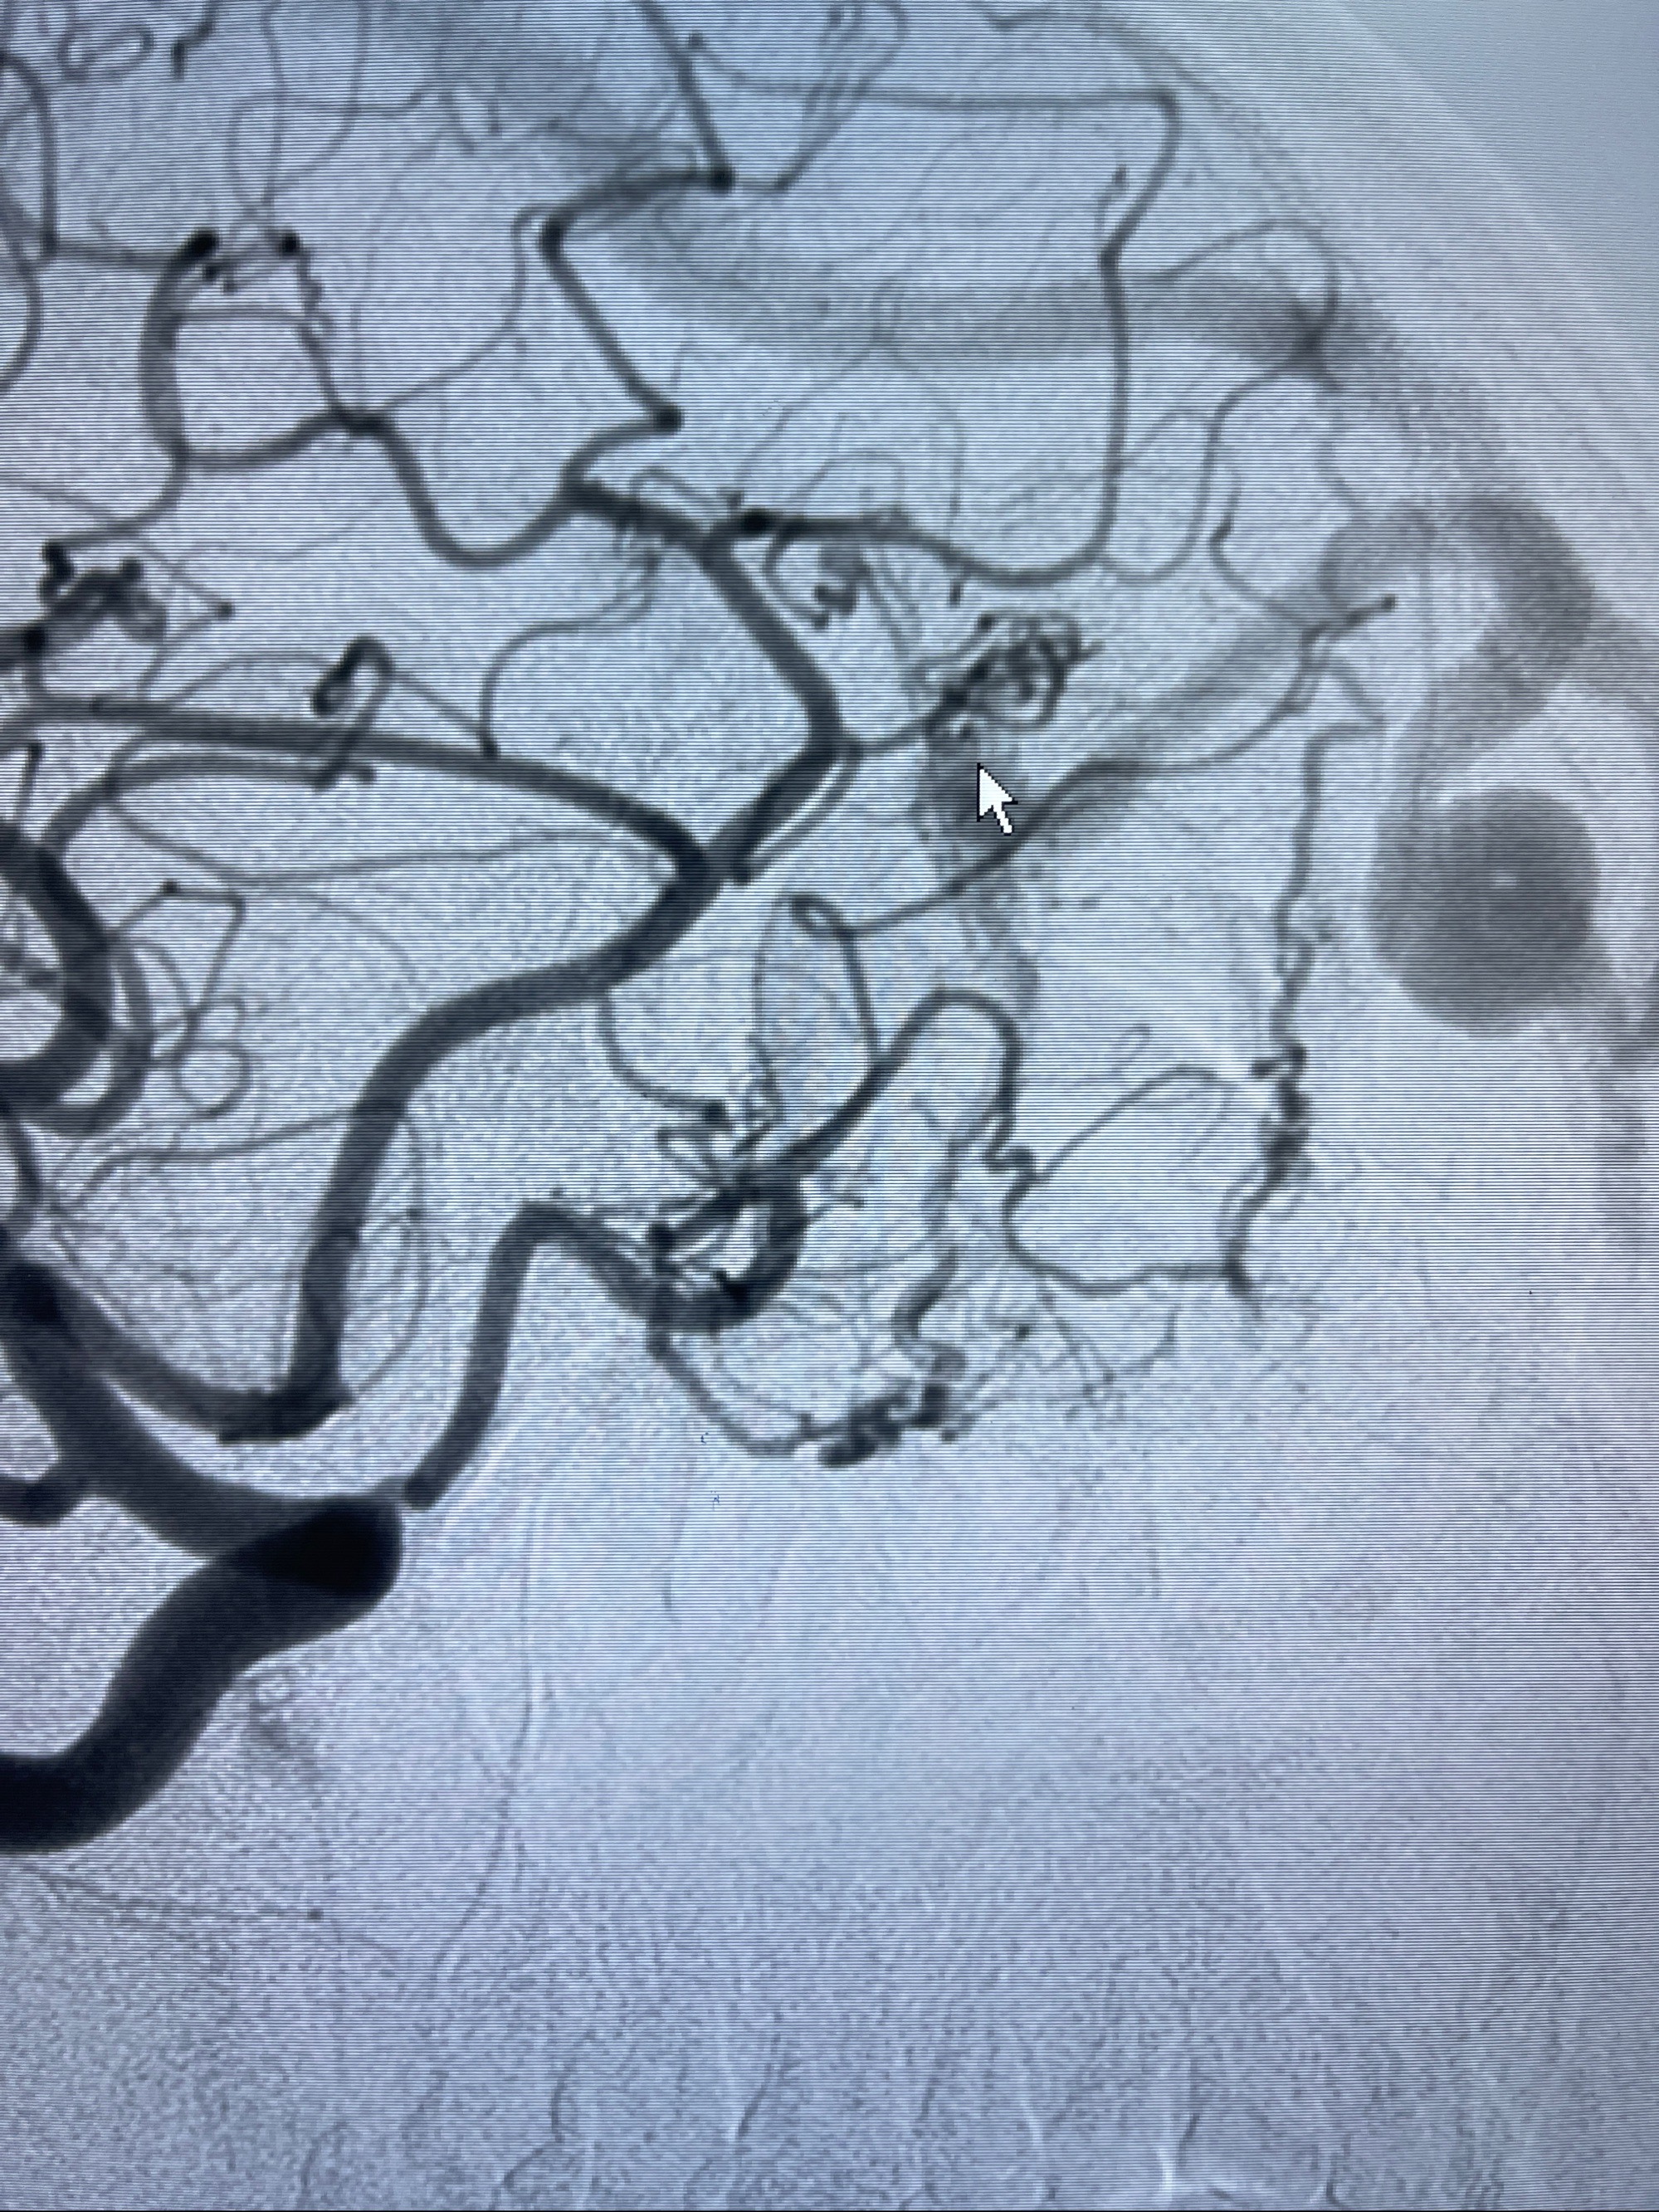

2023-09-13全脑血管造影:前颅底硬脑膜动静脉瘘,供血动脉为双侧胼周动脉、眼动脉脑膜支,静脉向上矢状窦方向引流